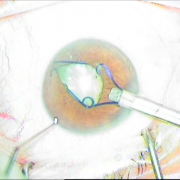

Δευτερογενής ανθέη φακού ιριδικής στήριξης

Δευτερογενής ένθεση φακού

ιριδικής στήριξης

Τομή Κερατοειδούς

Περιφερική Ιριδεκτομή

Ένθεση Φακού

Συρραφή Τομής